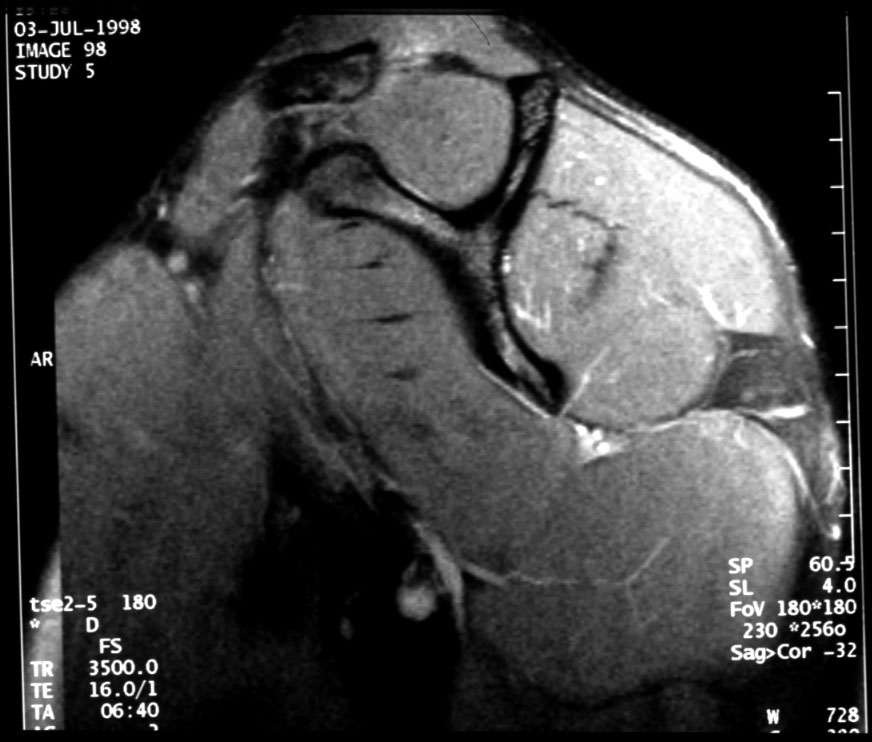

Normal MR of Left Shoulder (medial saggital) -- Identify: coracoid, spine

of scapula, clavicle, supraspinatus muscle, intraspinatus muscle, subscapularis

muscle